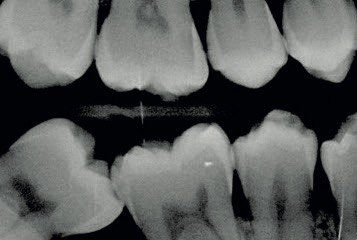

4. What surface require restoration?